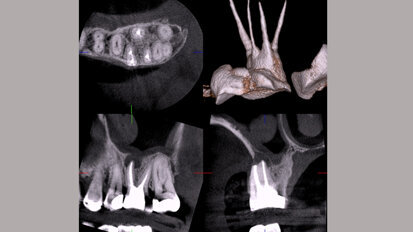

Cirugía implantológica avanzada

El experto en implantología oral Juan Manuel Aragoneses, Vicerrector Académico de IESO, de UNINCE y ex-Director de Odontología de la Universidad Europea ...